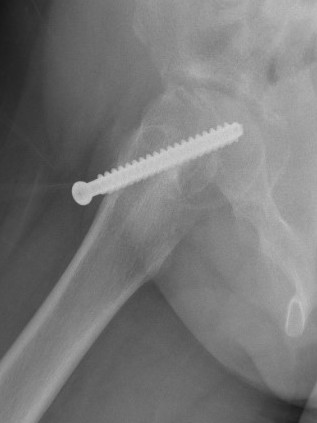

Subtrochanteric fracture

Subtrochanteric fracture likely causes by multiple drill holes / attempts

Cause

Too low screw entry

Multiple drill holes to get correct entry

Management

Intramedullary nail